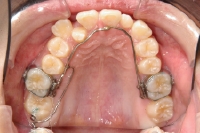

• 上顎の内側に装置

上顎の外側にセラミックブラケットを装着

下顎の奥歯にバンドを装着

• 下顎の外側にセラミックブラケットを装着